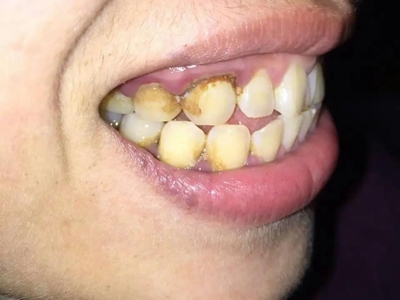

急性坏死性溃疡性龈炎症状图片

急性坏死性溃疡性龈炎起病急,病程短,常为数天至1-2周,以龈乳头和龈缘的坏死为其特征性损害,尤以下前牙多见,初起时龈乳头充血水肿,个别龈乳头顶端可发生坏死性溃疡,上覆有灰白色坏死物,中央凹下如火山口状。龈缘如虫蚀状,坏死区出现灰褐色假膜,擦去后可见出血创面。龈乳头被破坏后与龈缘成一直线,如刀切状。病损一般不波及附着龈,患处牙龈极易出血,疼痛明显并有腐败性口臭。

急性坏死性溃疡性龈炎是一种由多种微生物(如梭形杆菌、螺旋体等)引起的机会性感染,当宿主局部抵抗力降低时,这些微生物的毒性物质可形成组织病损。已存在的慢性龈炎或牙周炎是本病发生的重要条件。吸烟史、精神紧张、过度疲劳、营养不良、全身消耗性疾病等,易诱发本病。